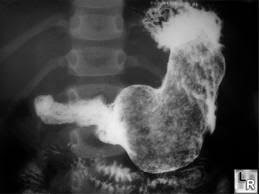

Barium swallow is considered an older technology for gastric cancer screening. The way it works is that the patient drinks an X-ray dye that coats the stomach. Then x-rays are taken that shows the stomach in outline (Figure 1). The radiologist then looks at this indirect outline of the stomach to look for growths or ulcers.

Figure 1: Barium Swallow outline of the stomach